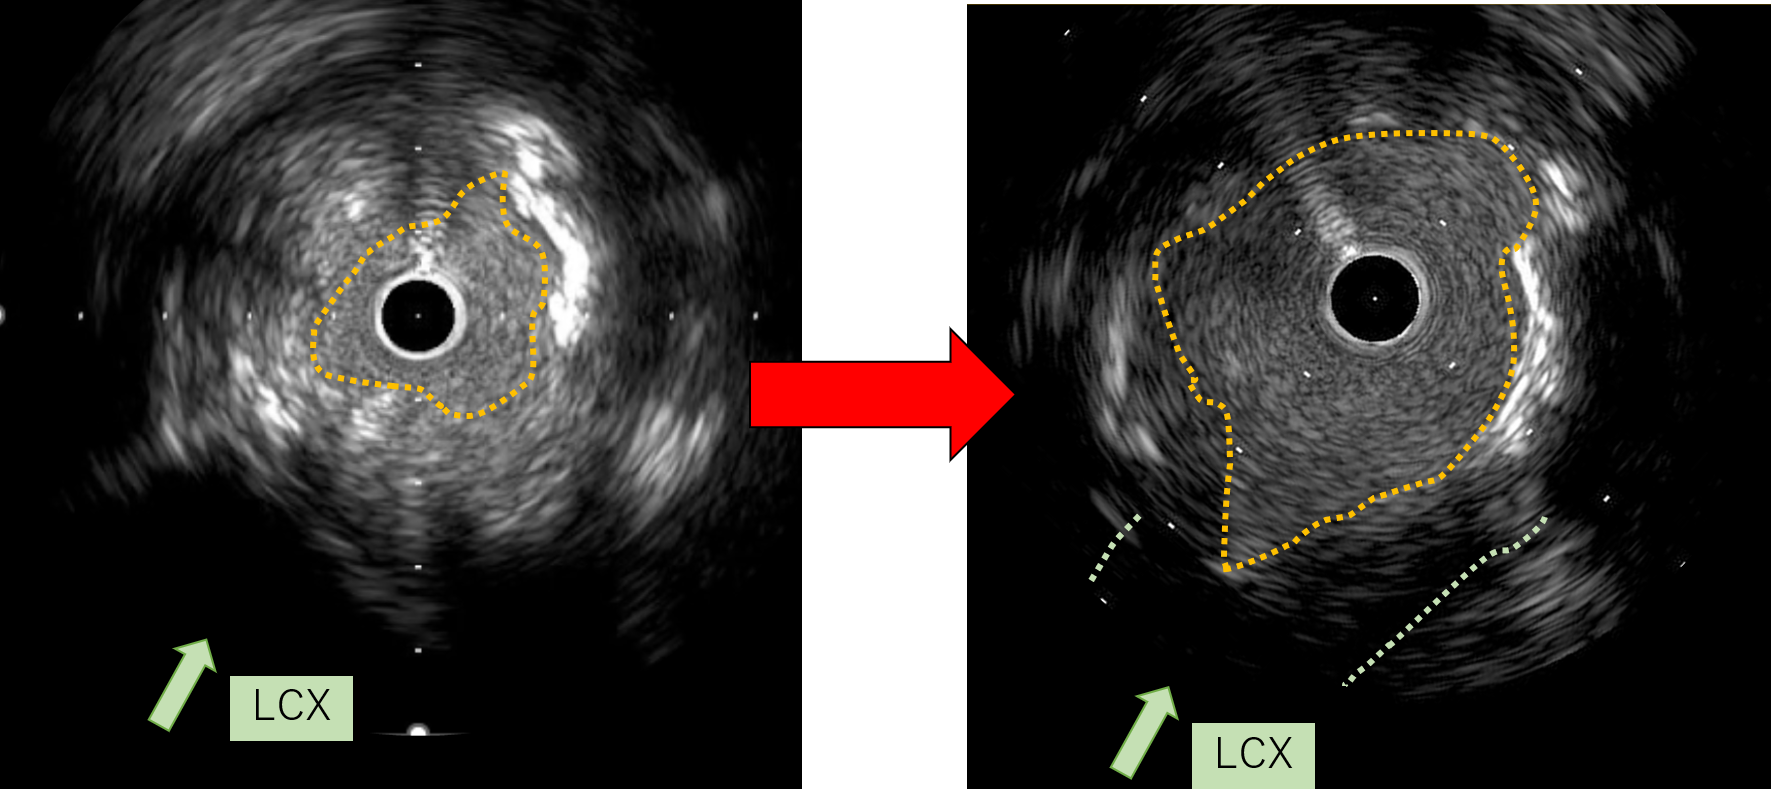

First, percutaneous coronary intervention (PCI) was performed toward the left anterior descending artery (LAD). The initial antegrade wire deviated from the true lumen; therefore, parallel wire technique was employed to achieve successful crossing. To avoid jailing the left circumflex artery (LCX) ostium, the stent was deployed precisely at the LAD ostium, and the left main trunk (LMT) was dilated using a 4.0-mm cutting balloon. One month later, intervention toward the LCX was undertaken. Intravascular ultrasound (IVUS) performed from the LAD confirmed achronic total occlusion (CTO) entry with a markedly thick plaque covering the LCX ostium. Although the lesion was accurately marked, penetration with a high-penetration guidewire was unsuccessful. Even with the balloon screen technique using a CP 8-20, wire penetration remained unsuccessful. Therefore, plaque debulking was selected to expose the CTO entry. Directional coronary atherectomy (DCA) was performed, and follow-up IVUS demonstrated significant plaquethinning compared with baseline. Subsequently, the CP 8-20 wire advanced smoothly, enabling successful wire crossing. The procedure was completed usinga mini-crush stenting strategy.

Aorto-ostial CTO of the LMT is extremely rare, accounting for approximately 0.1% of all CTOs. In this case, the lesion was particularly unique due to its unprotected LMT, absence of retrogradeoption, and completely separated distal bifurcation. In a bifurcation with separated branches, successful wire passage into one branch inevitably resultsin ¡°short-cut¡± the entry of the other branch. In this case, cutting angioplasty could not modify the cap; therefore, directional coronary atherectomy (DCA) was employed. Although DCA is currently approved only in Japan, the essential concept is targeted plaque modification at the entry, which may also be achieved with other atherectomy modalities.